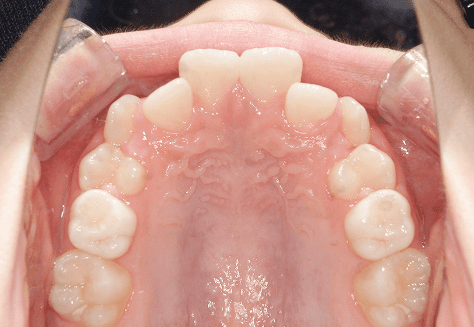

S.K

治療前

治療後

主訴

歯が重なっていて気になる。前歯が出ていて唇が閉じにくい。ハミガキがしにくい。

診断

上顎前突・叢生

年齢/性別

20代/男性

抜歯部位

上下第三大臼歯

使用装置

上下インビザライン

保定装置

上下ビベラリテーナー

料金

初回資料採得・・・・・・・30,000円

診断料・・・・・・・・・・33,000円

動的治療終了時資料採得・・5,500円 -

基本料金

990,000円

診察料金

1,100円×33回

治療期間

3年5カ月